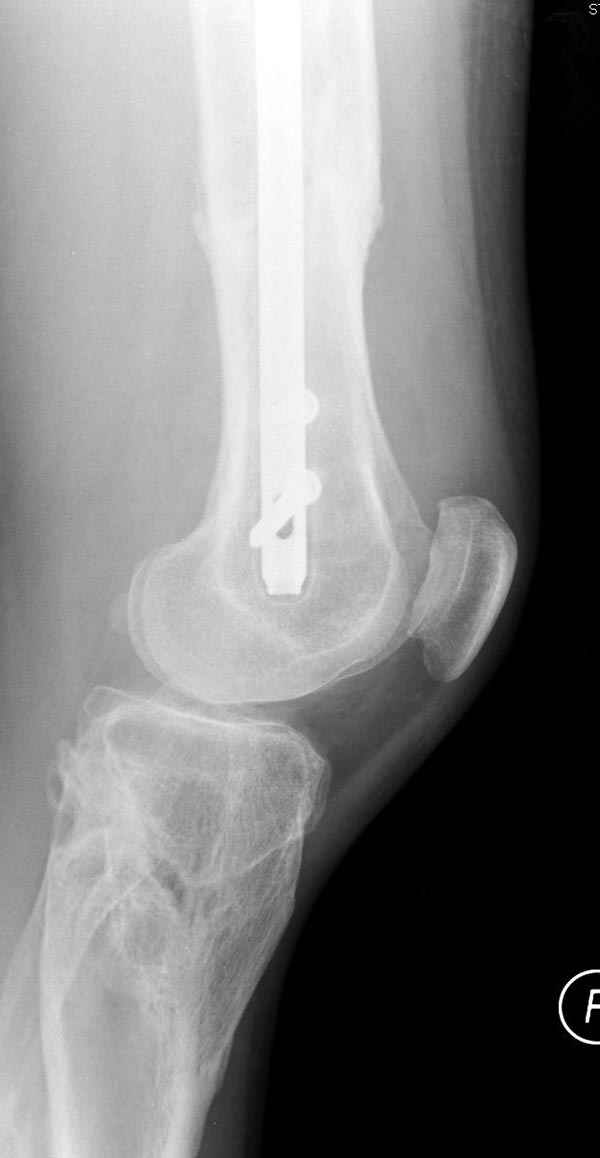

Мы не дождались “Happy End”, у больного IQ в пределах 70%, через 6 месяцев вернулся после небольшой травмы, споткнувшись получил перелом

того же бедра (рис №7).

На следующий день произвели интрамедуллярный остеосинтез: этапы во время операции (рис №8, №9)

и последующих снимках (рис №10, 11, 12, 13) перелом сростается и передвигается с полной нагрузкой.